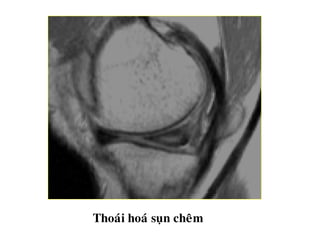

THOAÙI HOÙA SUÏN CHEÂM

Taêng tín hieäu beân trong suïn cheâm khoâng lieân quan

ñeán maët khôùp treân vaø döôùi.

Thoaùi hoaù suïn cheâm